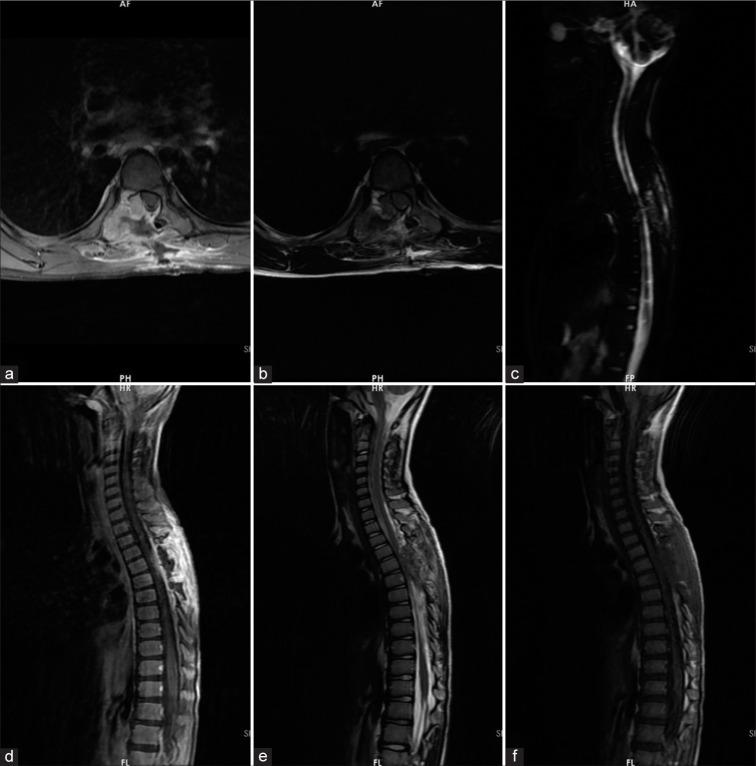

A 7-year-old boy presented with chest wall pain persisting for two months before admission, accompanied by progressive mono paresis lasting ten days before admission. Myelopathy signs were evident during the examination. Imaging confirmed a multicystic lesion at the T6 level involving the posterior elements of the vertebra, with significant cord compression. Due to deteriorating neurological function, he underwent urgent laminectomy and neural decompression, followed by subtotal tumor resection. Postoperative histopathological examination confirmed the diagnosis of an ABC, and the patient experienced significant neurological recovery. However, after 21 days, the patient was readmitted to the emergency department with severe paraparesis. Magnetic resonance imaging revealed rapid growth of the residual tumor, leading to cord compression. He underwent aggressive total tumor resection, T6 vertebral body corpectomy, and fixation with pedicle screws and cage insertion. Following the second surgery, prompt neurological recovery occurred.

一名7岁男孩入院前胸痛持续两个月,入院前还伴有进行性单瘫持续了十天。检查时脊髓病体征明显。影像学检查证实T6水平有一个多囊性病变,累及椎体后部结构,伴有明显的脊髓受压。由于神经功能恶化,他接受了紧急椎板切除术和神经减压术,随后进行了肿瘤次全切除术。术后组织病理学检查确诊为ABCs,患者神经功能有显著恢复。然而,21天后,患者因严重双下肢轻瘫再次入住急诊科。磁共振成像显示残留肿瘤迅速生长,导致脊髓受压。他接受了积极的肿瘤全切除术、T6椎体次全切除以及椎弓根螺钉固定和椎间融合器植入术。第二次手术后,神经功能迅速恢复。